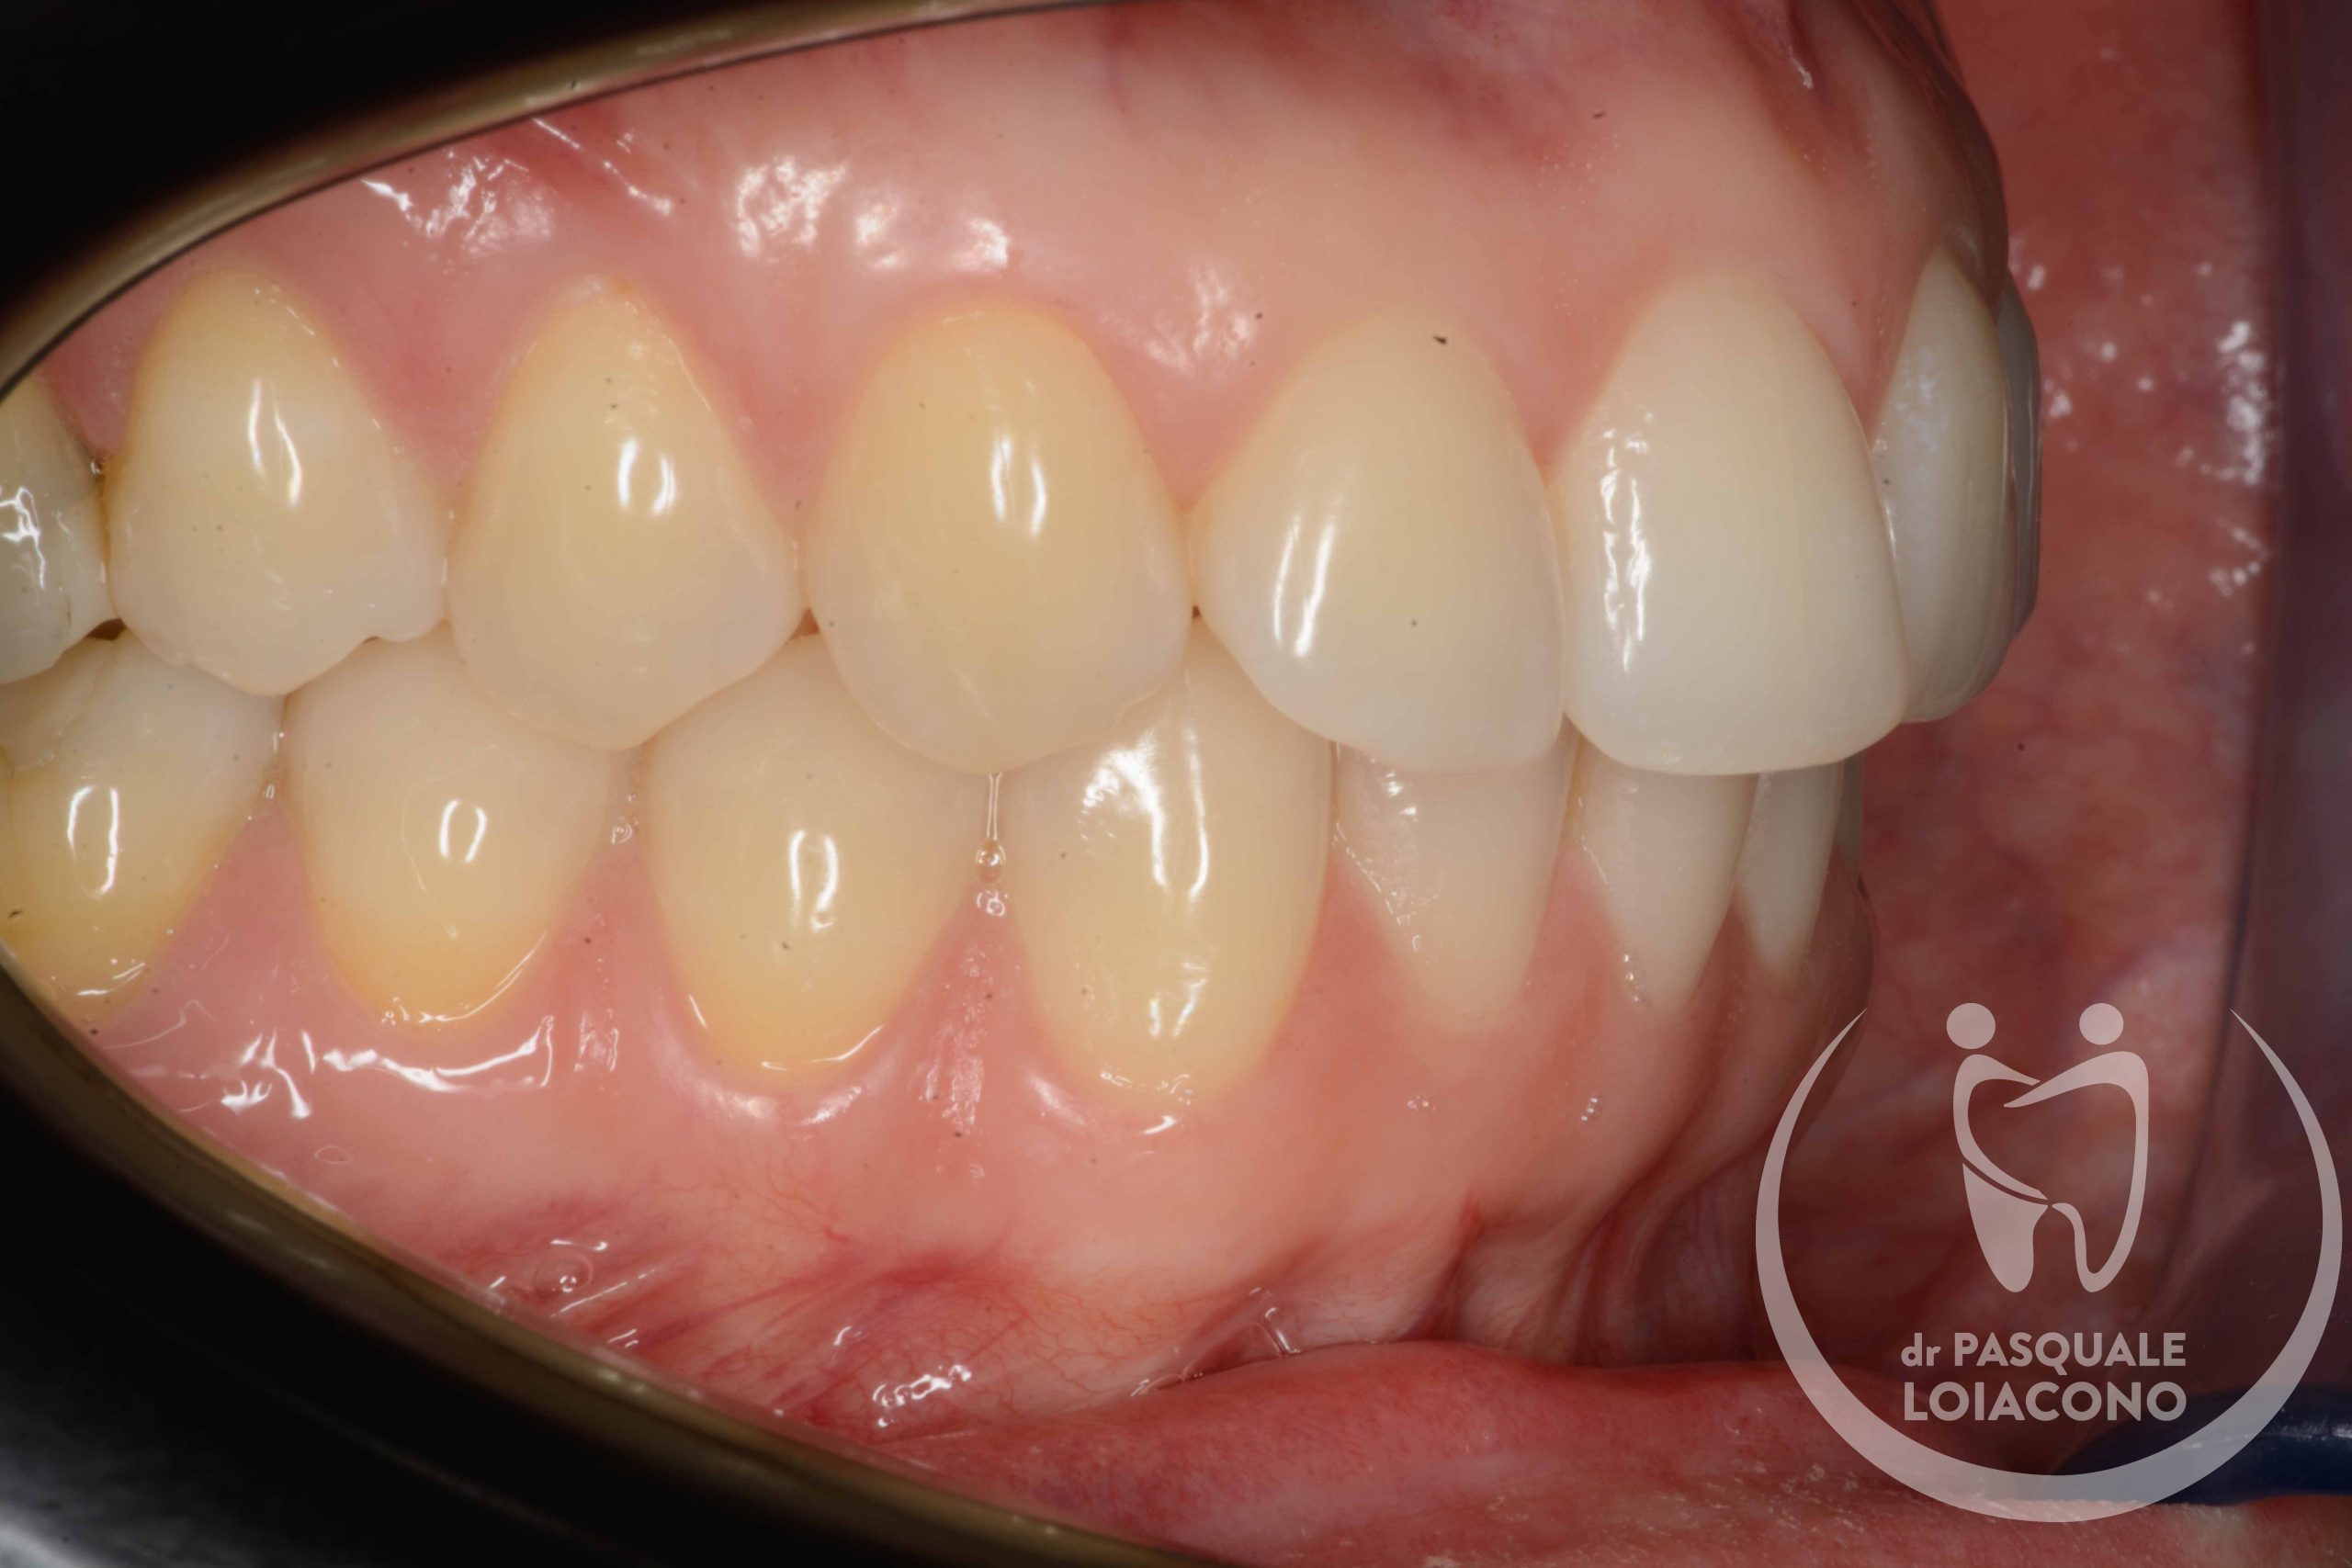

In generale nel funzionamento della bocca è preferibile che ci sia la simmetria tra le parti destra e sinistra, perché segno di equilibrio muscolare. Le asimmetrie delle arcate sono spesso la conseguenza di abitudini di masticazione prevalente su un solo lato, condizione non ottimale perché potrebbe creare tensioni nel nostro sistema posturale e sulle articolazioni della mandibola.

Quando ci sono problemi articolari della mandibola è necessario ricercare un’occlusione dentaria che rimetta il sistema il più possibile in equilibrio. L’organo della masticazione non è costituito solo da denti, ma anche da articolazioni e componenti neuromuscolari, e solo quando tuti i componenti sono in armonia tra loro si può avere salute e benessere. In realtà non tutti gli studiosi sono d’accordo su questioni fondamentali e non esiste visione unanime. Questo vuol dire che potreste incontrare un odontoiatra che sconsiglia qualsiasi trattamento, se non fisioterapia e massaggi o addirittura solo terapia psicologica di sostegno. All’opposto esistono scuole di pensiero che identificano nell’occlusione il fattore scatenante di una patologia che comunque resta complessa e multifattoriale. Da dentista desidero che la bocca funzioni bene e segua le regole stabilite, perché considero comunque positiva questa condizione, e quindi cerco di riportare l’occlusione del paziente verso una condizione il più possibile ideale.